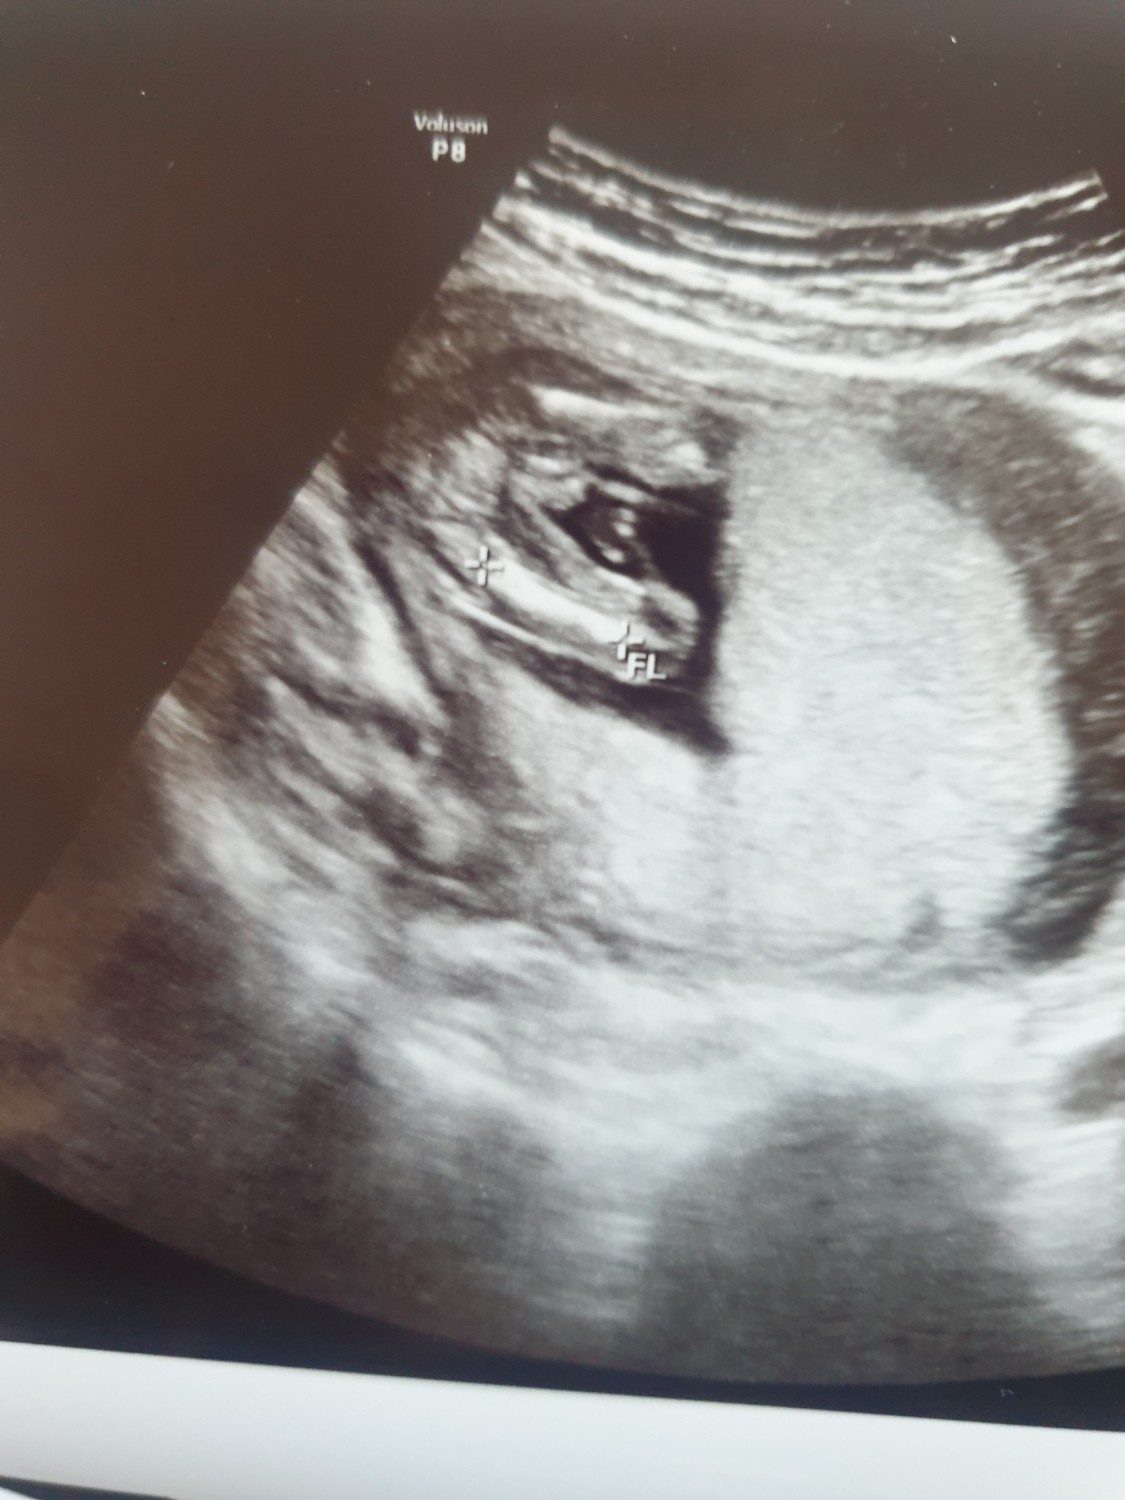

รบกวนดูภาพอัลตร้าซาวน์ของน้องหน่อยค่ะว่าเป็น ชายหรือหญิง

น้องเป็นเด็กหลอดแก้วใส่ตัวอ่อน 2 แต่ได้มา 1 ค่ะ ตรวจนิฟตี้เรียบร้อยแล้วแต่ว่าประเทศที่อาศัยอยู่ห้ามคุณหมอบอกเพศค่ะ เป็นเรื่องผิดกฎหมาย จากรูปอายุครรภ์ 15 สัปดาห์ค่ะ ขอบพระคุณล่วงหน้าสำหรับความเห็นทุกๆ ท่านค่ะ